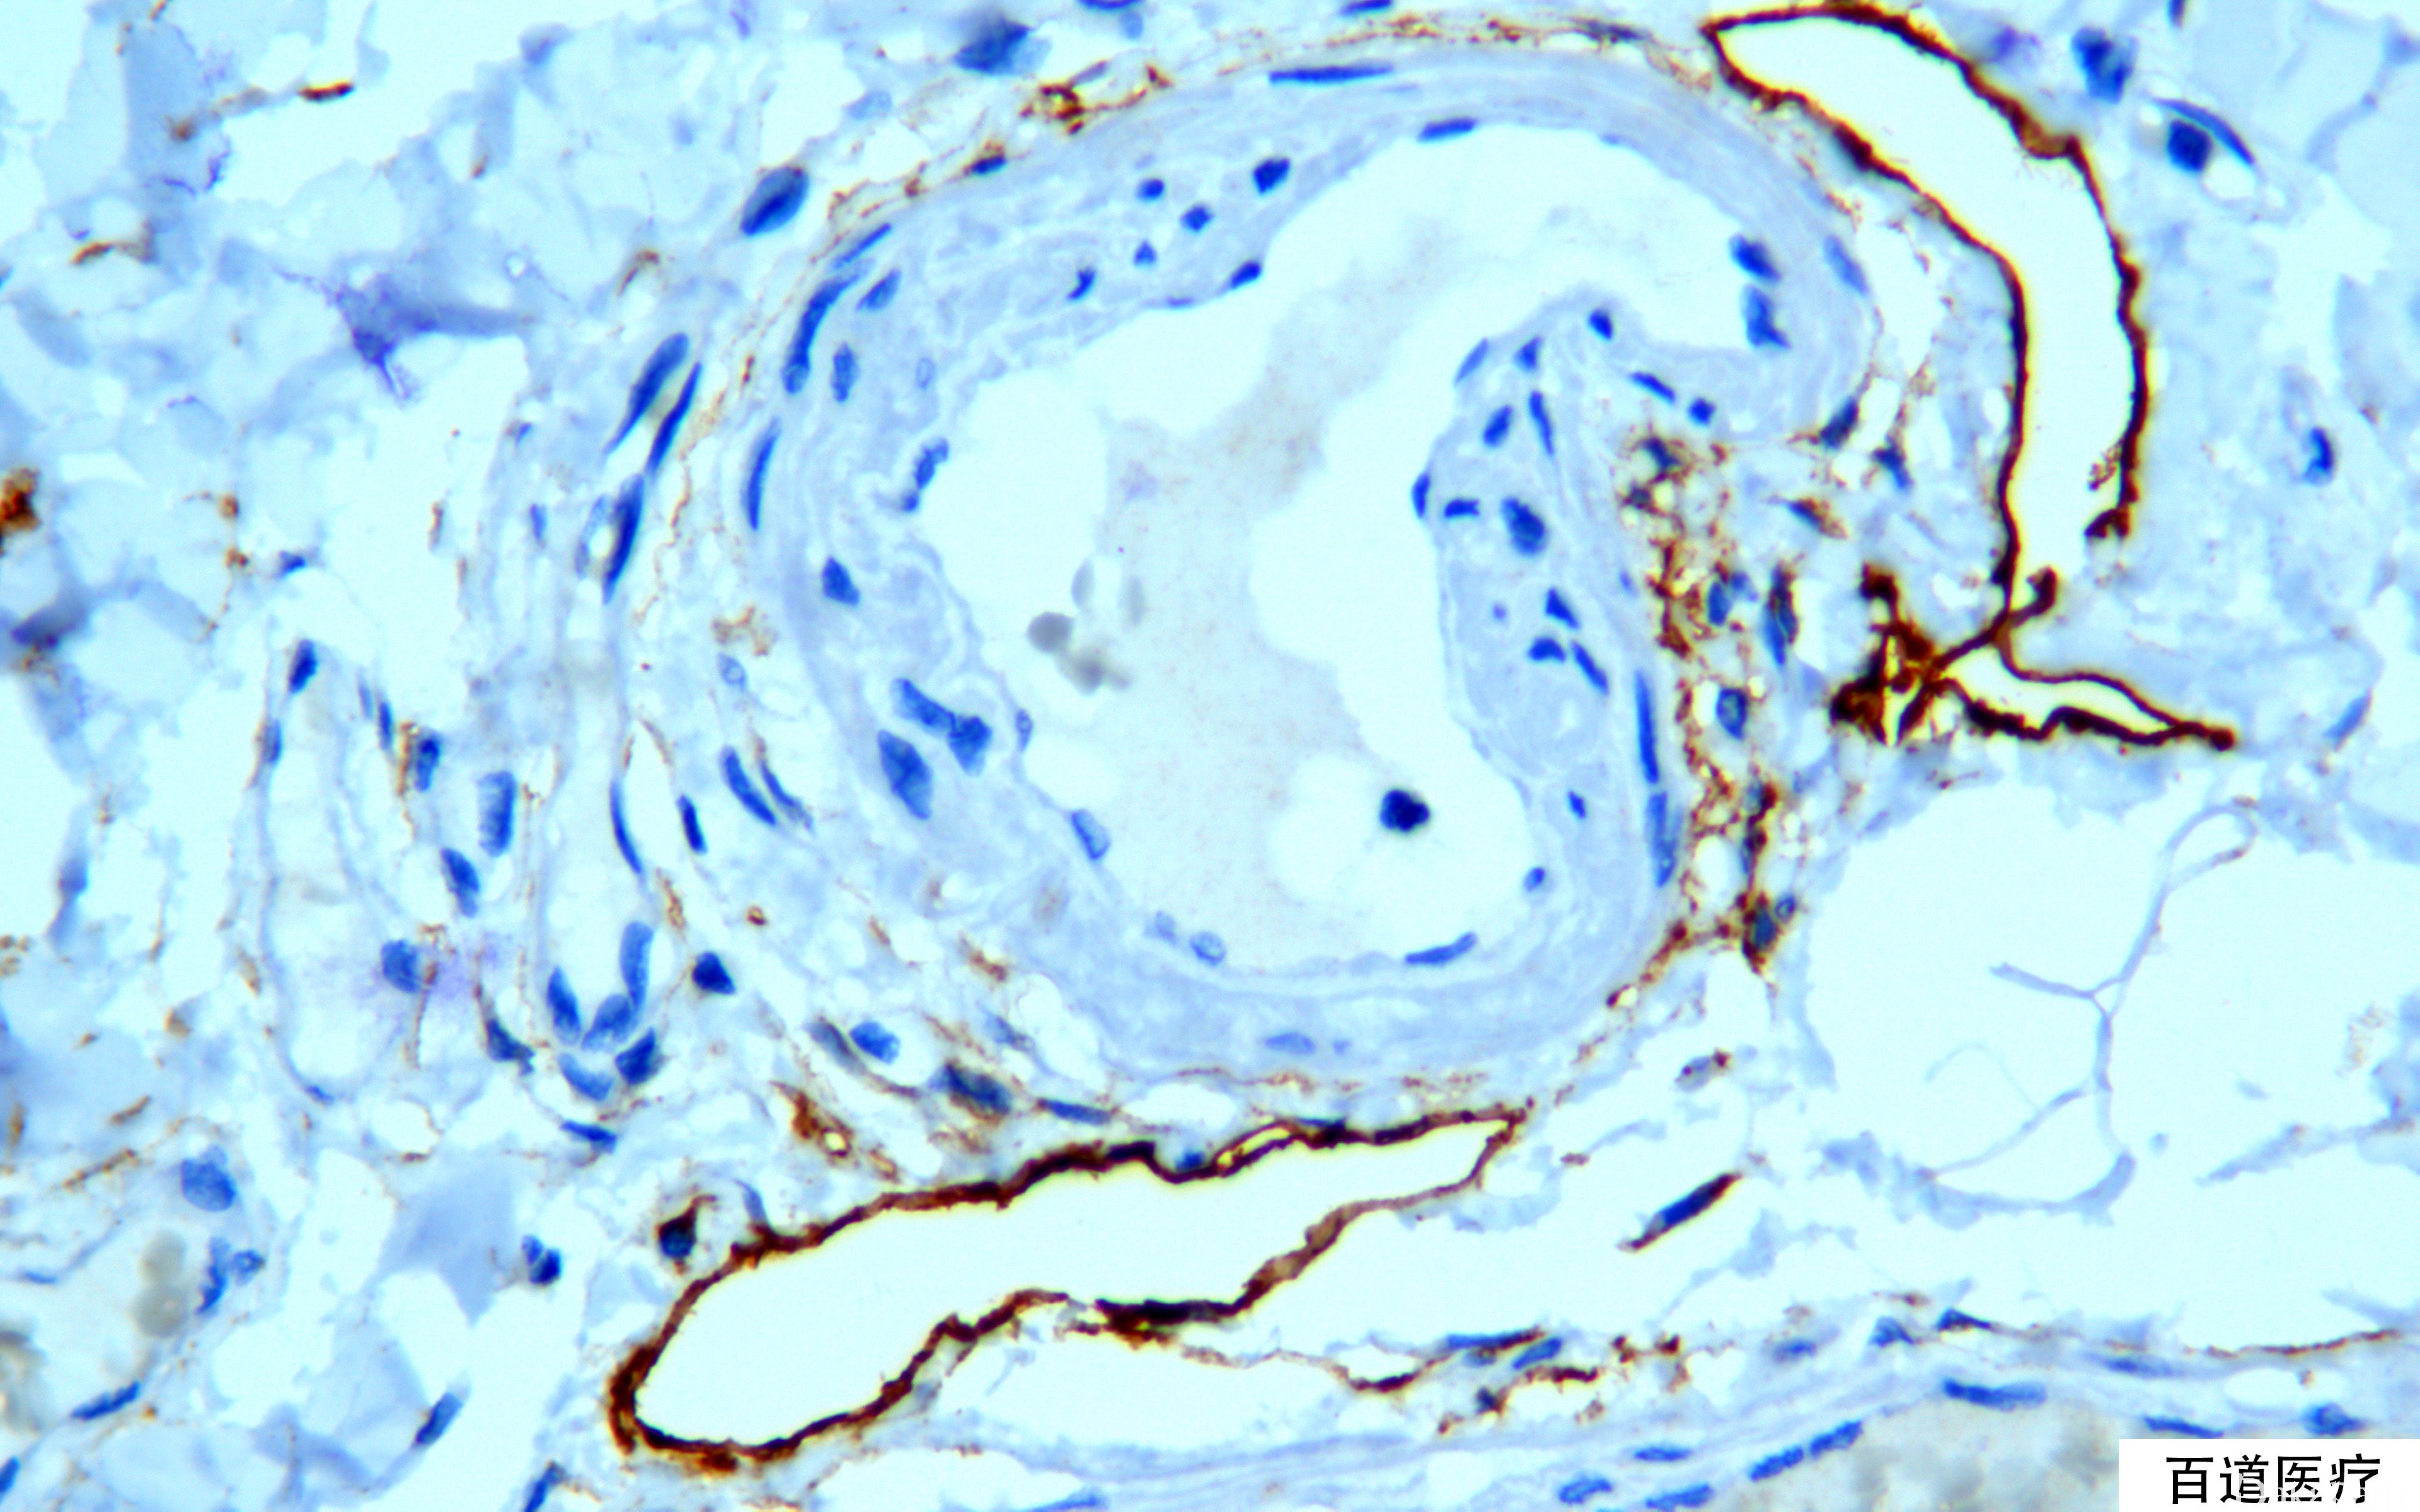

Podoplanin

别名: D2-40;M2A

膜黏蛋白,标记淋巴管内皮细胞而不标记血管内皮细胞

确定淋巴管内癌栓,与血管内癌栓鉴别;